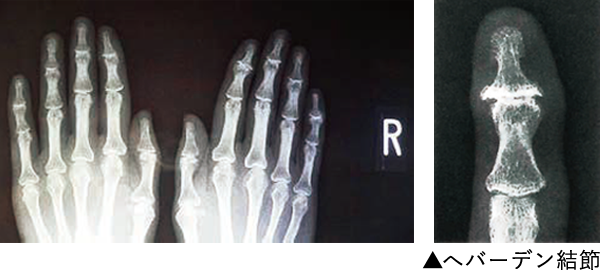

へバーデン結節の診断は、視診、触診などの理学所見(診察)とX線による画像診断が行われます。

症状の項で示しましたように、DIP関節(1番指先の関節)の腫れや熱感、変形、動きの悪さ、痛みの有無を診察することのほか、X線では、関節の間隙(骨と骨の間)が狭くなったり、関節が壊れたり、骨のとげ(骨棘といいます)が突出するなどの、いわゆる変形性関節症の所見があれば、へバーデン結節と診断されます。

またX線でもリウマチの場合は骨が炎症によって溶けてゆくのに対して、へバーデン結節では、骨が負担などにより増殖している(骨棘など)像が診られるため、区別することができます。